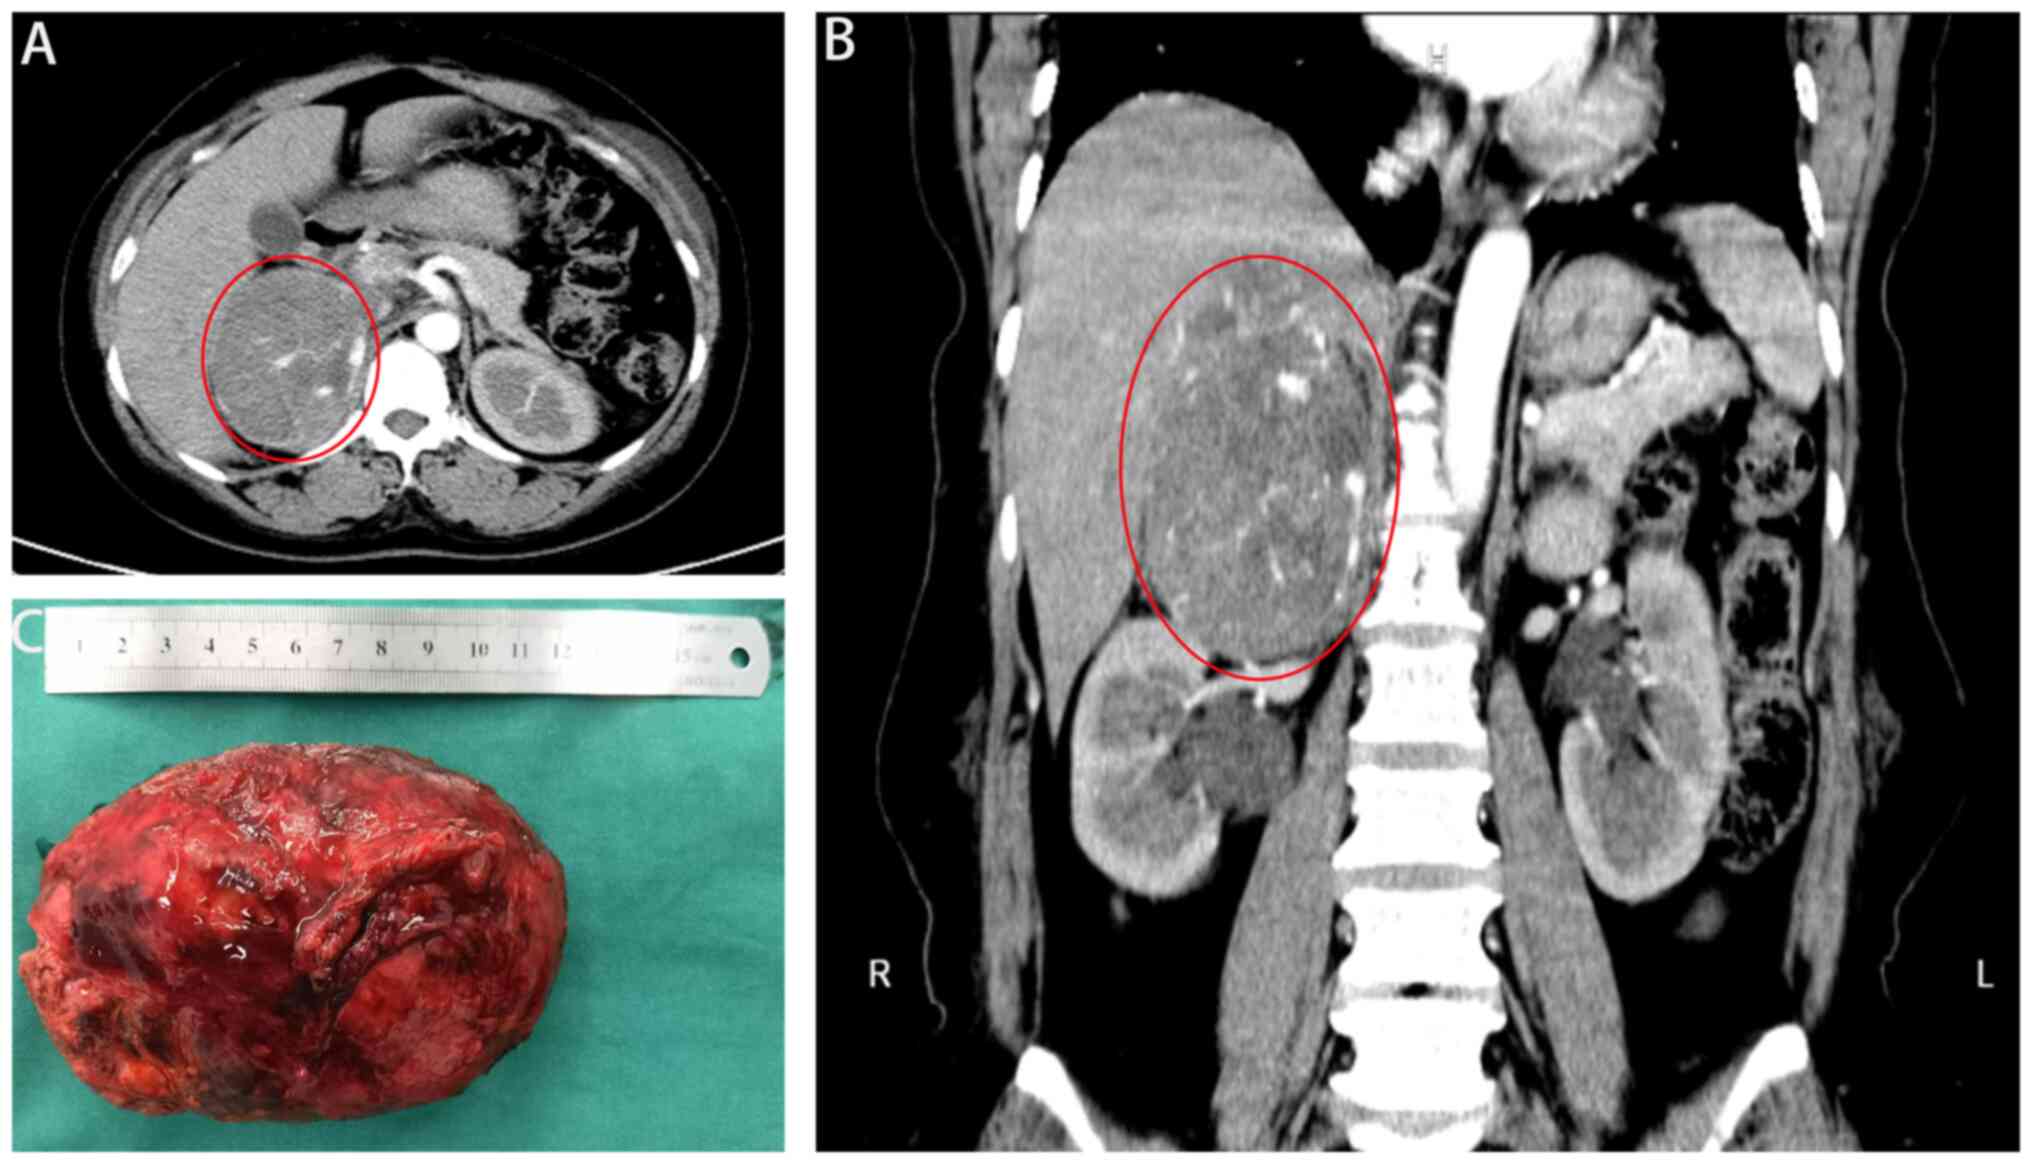

Adrenal cortical carcinoma with non‑islet cell tumor hypoglycemia: A case report

Adrenal cortical carcinoma (ACC) is a rare invasive cancer with a poor prognosis. ACC often manifests with hyperglycemia and Cushing syndrome. Hypoglycemia is an unusual manifestation of this malignant tumor; therefore, the diagnosis and management of patients with ACC and hypoglycemia is extremely challenging. The current study presents the case of a 53‑year‑old woman who experienced recurrent, uncontrolled hypoglycemia and episodes of hypoglycemic coma. The patient was diagnosed with right‑sided ACC and successfully treated with surgery. Hypoglycemic episodes associated with ACC are extremely rare. Moreover, the clinical diagnosis is often challenging owing to its similarity to multiple other diseases. Recurrent severe hypoglycemic comas, if not addressed promptly, can lead to patient death. Therefore, it is necessary to monitor patients with such rare diseases in clinical practice and make an accurate diagnosis promptly to ensure timely and effective treatment. This report of an ACC case with non‑islet cell tumor hypoglycemia aims to raise awareness among clinical physicians.

Figure 1